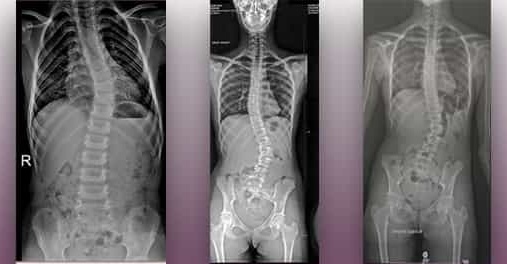

La scoliosi idiopatica consiste in una deviazione laterale della colonna vertebrale.

In secondo luogo, secondo il grado di curvatura raggiunto dalla colonna vertebrale scoliotica, il Filum System® può arrestare il suo peggioramento o persino permettere che, dopo la liberazione chirurgica, le curvature patologiche si correggano in certa misura.

Inoltre, anche nei casi con scoliosi severe e irreversibili (poiché con più di 40 gradi di curvatura interviene anche il fattore della forza di gravità), il nostro metodo ha ugualmente dei risultati eccellenti nella riabilitazione posteriore all’operazione, dato che- dopo la liberazione del midollo, migliorando la clinica dei malati (sintomatologica e neurologica)– i pazienti si sentono meglio una volta in fisioterapia, e ottengono migliori risultati che senza l’applicazione del metodo.